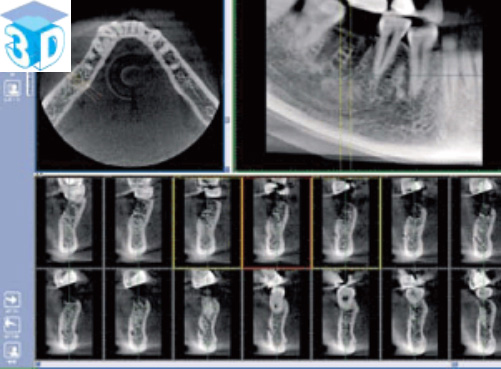

上図のような歯科用CTから得られる三次元的情報は、インプラント治療、歯周病治療、根管治療親知らずの抜歯など歯科治療のあらゆる分野での診断に必要不可欠なものとなってきています。詳しくはGCホームページをご覧ください。